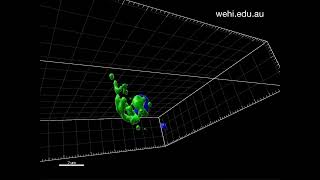

Malaria parasites blocked from invading red blood cells 3D visualisation shows how inhibitor WM382 blocks malaria parasites from invading red blood cells

3D visualisation shows how inhibitor WM382 blocks malaria parasites from invading red blood cells C. Chitnis - Red cell invasion by malaria parasites: from Basic Biology to vaccine development

Malaria parasites blocked from invading red blood cells 3D visualisation shows how inhibitor WM382 blocks malaria parasites from invading red blood cells

3D visualisation shows how inhibitor WM382 blocks malaria parasites from invading red blood cells C. Chitnis - Red cell invasion by malaria parasites: from Basic Biology to vaccine development